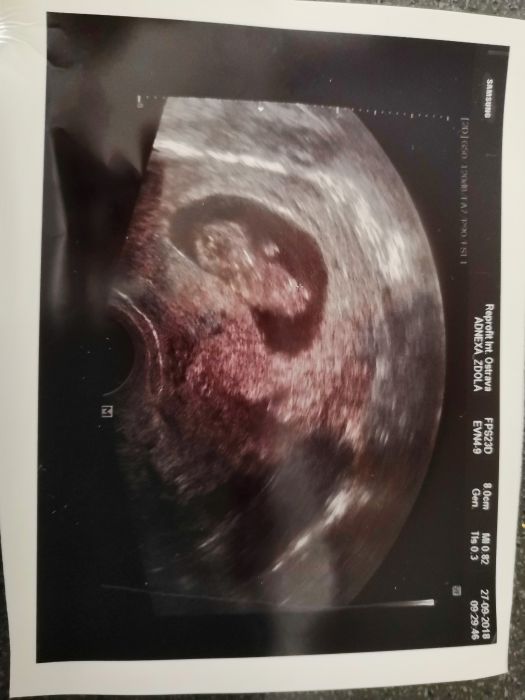

[1100239] Nestresuj se, vím, že se to lehce řekne, ale skus se netrápit. Já těhu příznaky taky moc nemám, až na dnešek, to je mi špatně. Ale jinak mi blbě nebývá. A dnes na kontrole vše v pořádku. Dle uzv 8+1, to je o 2 dny míň než dle ms, ale sedí to dle ovu. Už mi i vystavili průkazku a 12. jdu na odběry a kontrolu a 29. na velký uzv. Už se nemůžu dočkat.

Ahoj Kači, já byla v úterý poprvé... Podle kalkulačky bych na tom měla být jak ty, ale dle ultrazvuku jsme o 3 dny pozadu... Takze dnes 7+1 ... Ja su tedy na neschopence... Mám nařízen klid, kvůli hematomu kousek od cvrčka.. Ve čtvrtek jdu znovu na kontrolu, tak uvidíme jak to dopadne... Snad dobře.. Fotku mi ještě nedala, ale srdíčko jsem už viděla, jak pěkně mrkalo ... Chudák polovička celou dobu seděl v čekárně a nakonec ho ani dovnitř nevzali se na mrňouse podívat...